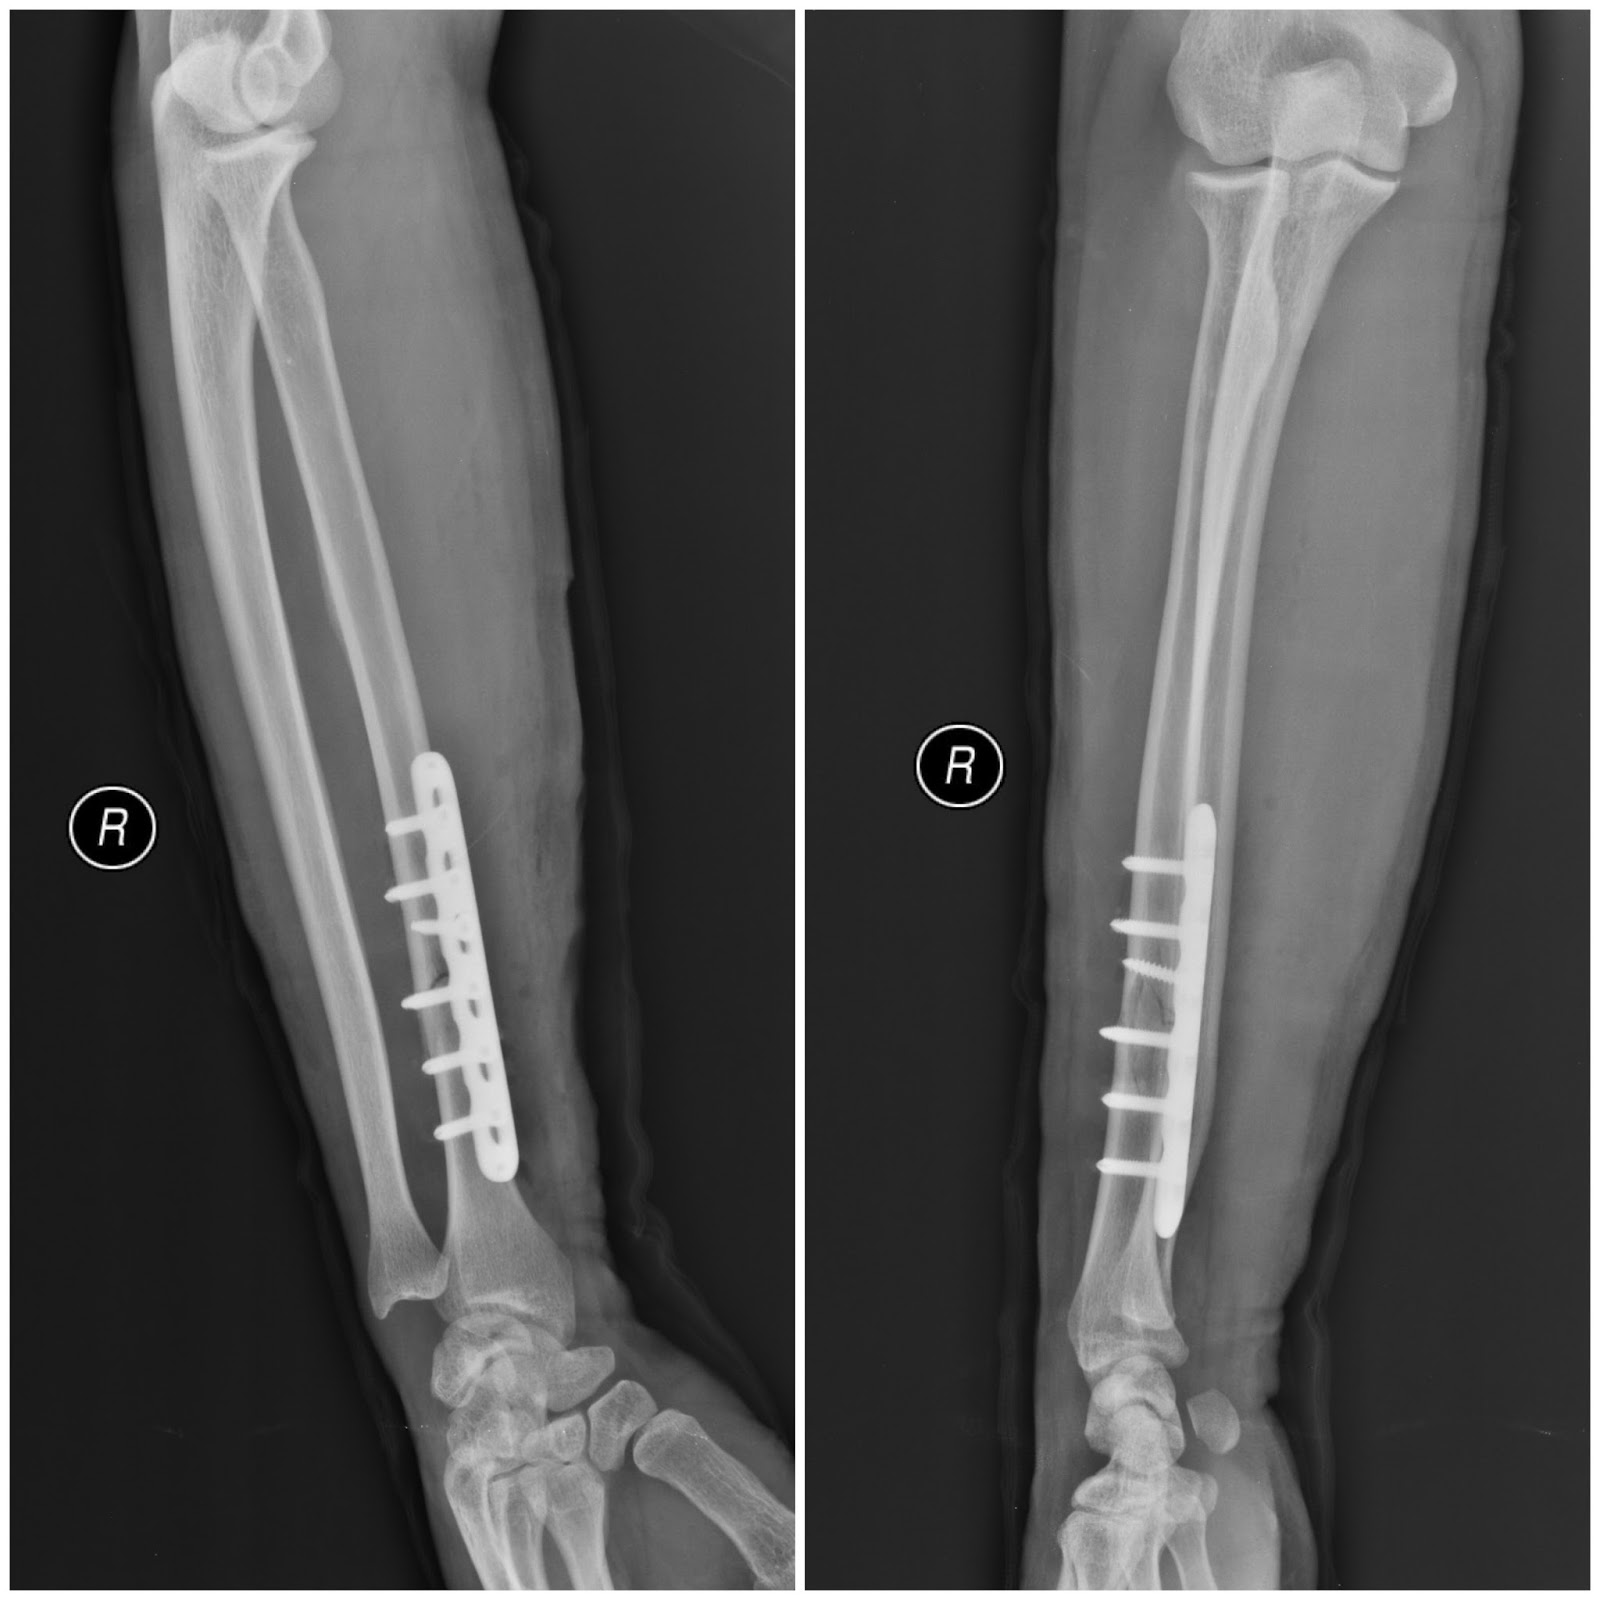

Source : pinterest.com